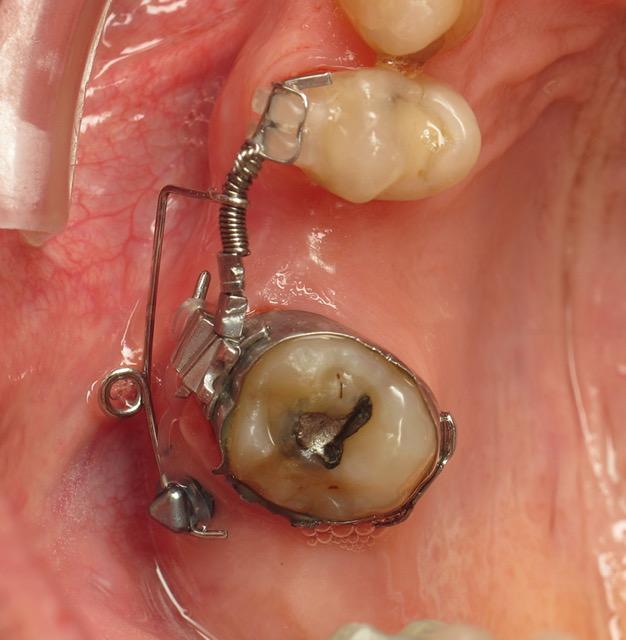

Cas 3 : ouverture d’espace et uprighting molaire mandibulaire avec préservation des compensations antérieures de classe III

L’originalité de ce cas est dans l’utilisation d’un accessoire collé pour stabiliser la prémolaire (on est en compensation de classe 3 avec une grosse linguoversion incisive) et d’un sectionnel Burstone sur la même minivis.

Un début de mouvement a été effectué avec une position rétro molaire de la minivis puis elle a été repositionnée en lingual... ce qui est peu commun voir dangereux pour un poseur non aguerri... mais cela a permi de gérer le sens transversal.